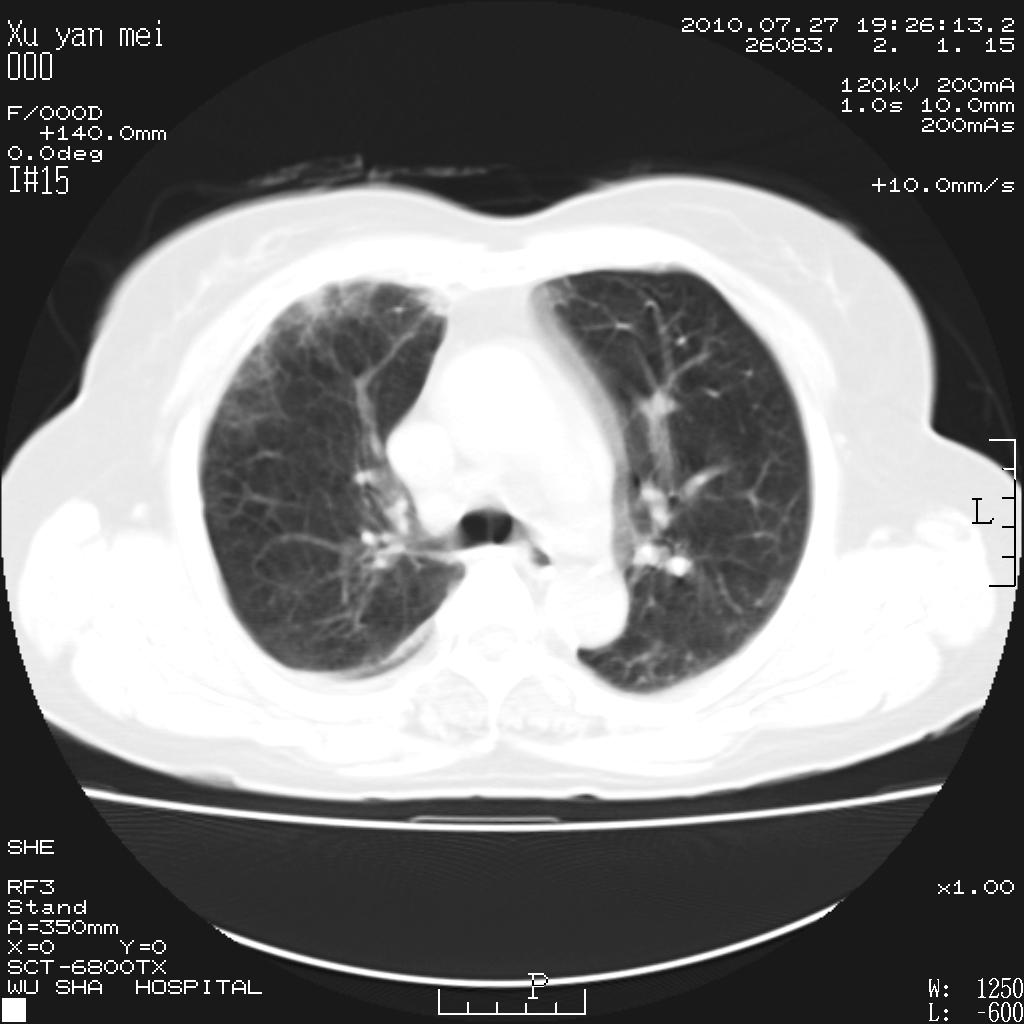

女,60岁,胸痛就诊,右肺结核?炎症?其它?(胸片右侧中上肺野确实看不到什么啊)

1)考虑两肺感染性病变;建议抗炎治疗后复查。2)双侧少量胸腔积液。

1)考虑两肺感染性病变;建议抗炎治疗后复查。2)右侧少量胸腔积液。

双肺炎症可能性大,建议抗炎后复查。右侧胸腔少量积液。双侧胸膜轻度增厚。

考虑两肺感染性病变;不除外肺栓;建议抗炎治疗后复查。